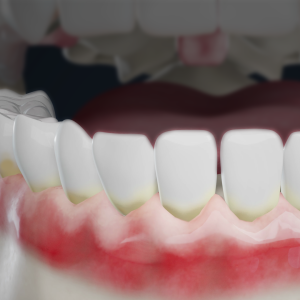

Digital Dental X-Rays: What They Tell Us About Your Smile and Oral Health

Digital X-rays help your dentist detect concerns early, track changes over time, and personalize your care…